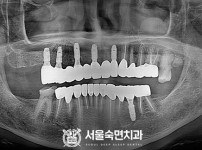

임플란트-전후사진3